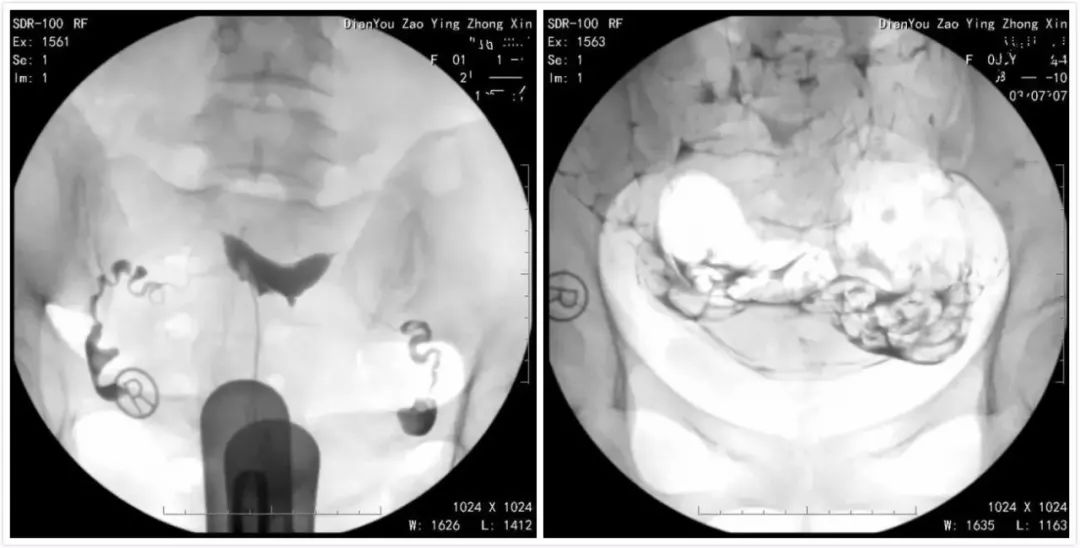

造影技術(shù)是一種通過(guò)特殊手段將某種物質(zhì)引入體內(nèi),以顯示某些器官或結(jié)構(gòu)的形態(tài)、位置及功能狀況的方法,在婦科領(lǐng)域,造影技術(shù)常用于檢查輸卵管、子宮等生殖器官的狀況,為不孕癥的診斷提供重要依據(jù),造影技術(shù)包括輸卵管造影、子宮造影等,這些檢查方法有助于醫(yī)生了解患者的生育能力狀況,從而制定相應(yīng)的治療方案。